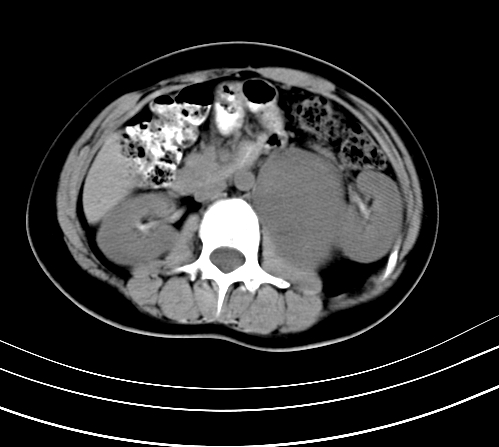

静脉期